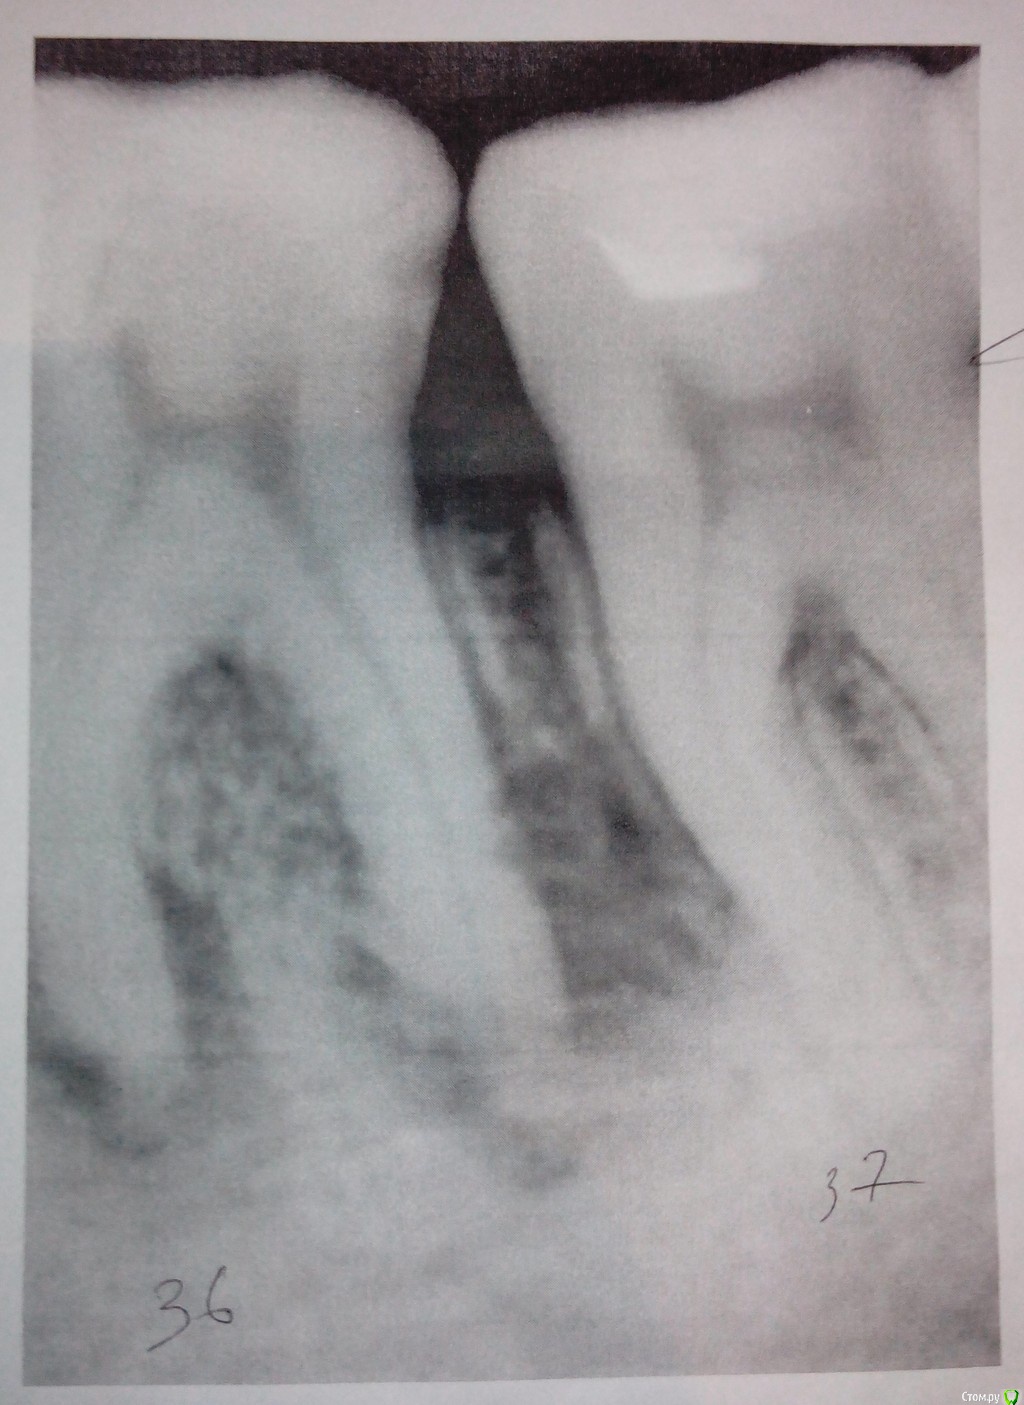

Чебурек Опубликовано 5 ноября, 2015 Автор Поделиться Опубликовано 5 ноября, 2015 еще такой есть снимок. Ссылка на комментарий

IvanK Опубликовано 5 ноября, 2015 Поделиться Опубликовано 5 ноября, 2015 Лечение 36Восстановление контактного пункта 36, 37 Ищите терапевта 3 Ссылка на комментарий

Чебурек Опубликовано 6 ноября, 2015 Автор Поделиться Опубликовано 6 ноября, 2015 Лечение 36Восстановление контактного пункта 36, 37 Ищите терапевта Врач говорит, что шанс на успешное лечение меньше 50%. Как считаете? Ссылка на комментарий

IvanK Опубликовано 6 ноября, 2015 Поделиться Опубликовано 6 ноября, 2015 Врач говорит, что шанс на успешное лечение меньше 50%. Как считаете?сходите еще на пару консультаций 100% успех Вам никто не предложит.. 1 Ссылка на комментарий